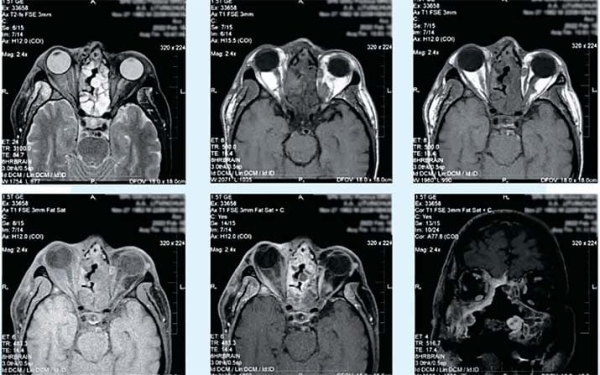

Магнитно-резонансная визуализация покажет степень и специфику распространения остеонекроза (см. фото 4).

Фото 4. МРТ орбит с контрастированием. Правосторонний экзофтальм. Ретробульбарная клетчатка с признаками отека. На фоне МР-отека мягких тканей интраорбитально в нижних и медиальных отделах правой орбиты определяются тканевые массы. Отсутствие контрастирования медиальной прямой мышцы справа. Незначительное скопление жидкости. Тканевые массы интимно прилежат к зрительным нервам сразу после выхода из зрительных каналов и ВСА на уровне отхождения глазничной артерии.